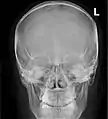

Paranasal sinuses

Paranasal sinuses seen in a frontal view

CT scans, radiographs (x-ray) and other illustrations